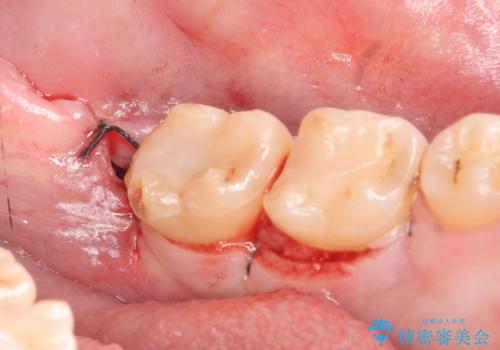

術後歯肉の回復を待ち、左下6はセラミックインレー、左下7はオールセラミッククラウンにて補綴しました。

オールセラミッククラウン(エコノミー)はスタンダード以上と違い、一塊となっているため欠けてしまうリスクが低いのが特徴です。

しかしその反面選択できる色の種類が少なく、色合いも単調であるという欠点もありますが、今回のケースのように前後の歯がクラウンの場合などでは十分に審美的な補綴が可能となります。